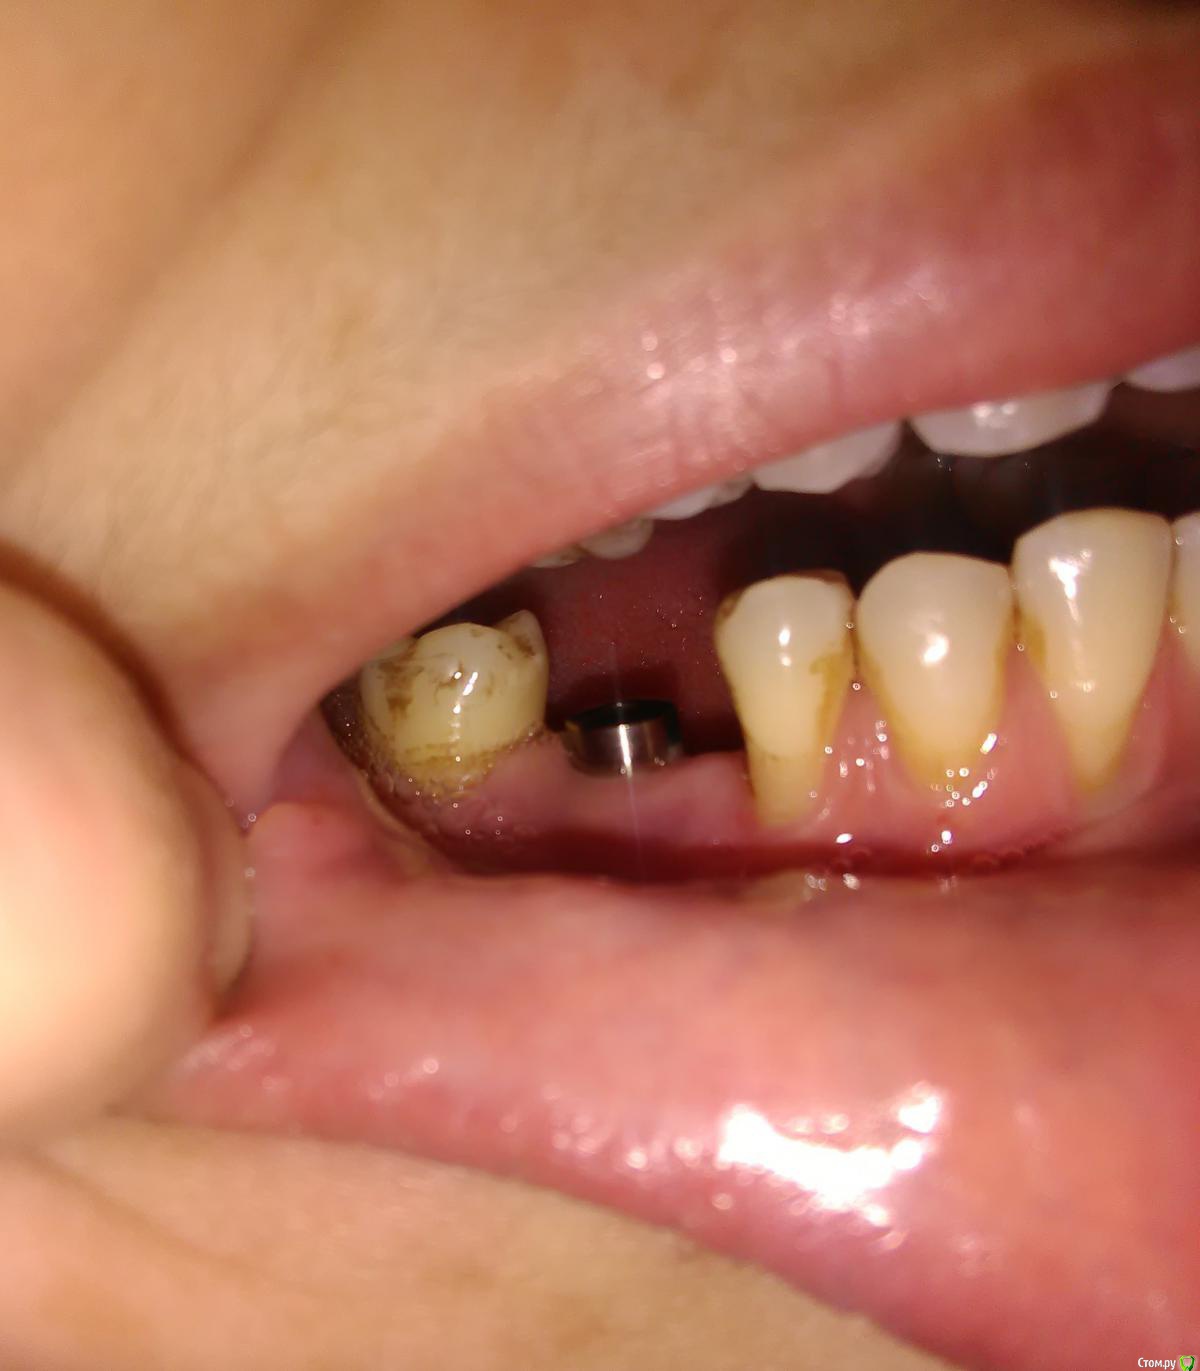

akburan Опубликовано 8 февраля, 2017 Поделиться Опубликовано 8 февраля, 2017 Установили имплант 3 мес. назад. Имплант прижился.Одновременно с имплантацией провели синус-лифтинг. До операций имела также место рецессия десны. Но через 3 недели после установки и подсадки костн. материала десна опустилась еще ниже в области импланта и 3.5 зуба, из-за чего мне кажется, что внедрили мало костного материала. С этой жалобой обращалась к хирургу неоднократно, на что он отвечал что все хорошо и десна со временем САМА восстановится. В данный момент уже сняли слепки для дальнейшего протезирования, но мне состояние десны категорически не нравится и я хочу что-то с этим сделать. Можно ли восстановить десну в обл. импланта? Возможно ли не извлекать при этом имплант? Поможет ли лоскутная операция в том смысле, что прирастет ли лоскут к импланту? Ссылка на комментарий

Bier Опубликовано 8 февраля, 2017 Поделиться Опубликовано 8 февраля, 2017 а что вам не нравится? Платформа имплантата не видна, по высоте десна есть. Объем? Ссылка на комментарий

Доктор Добрых Дел Опубликовано 8 февраля, 2017 Поделиться Опубликовано 8 февраля, 2017 Я бы рекомендовал Вам закрыть рецессии (оголенные корни) в области 43,44,45 зубов. 1 Ссылка на комментарий

akburan Опубликовано 9 февраля, 2017 Автор Поделиться Опубликовано 9 февраля, 2017 а что вам не нравится? Платформа имплантата не видна, по высоте десна есть. Объем?Не нравится то как нарастили кость или лучше сказать недорастили, мне кажется недоложили костного материала, а также десна у основания соседнего зуба, там до этого она не была так опущена и зуб начал пошатываться. Я бы рекомендовал Вам закрыть рецессии (оголенные корни) в области 43,44,45 зубов.Это тоже в планах, а вот как быть с имплантом, возможно ли у его основания уже после протезирования приподнять десну тоже? Ссылка на комментарий

DrNice Опубликовано 9 февраля, 2017 Поделиться Опубликовано 9 февраля, 2017 Не нравится то как нарастили кость или лучше сказать недорастили, мне кажется недоложили костного материала, а также десна у основания соседнего зуба, там до этого она не была так опущена и зуб начал пошатываться. Это тоже в планах, а вот как быть с имплантом, возможно ли у его основания уже после протезирования приподнять десну тоже? Десну приподнять можно, но я опять повторюсь, мне не нравится кость вокруг имплантата. Ссылка на комментарий